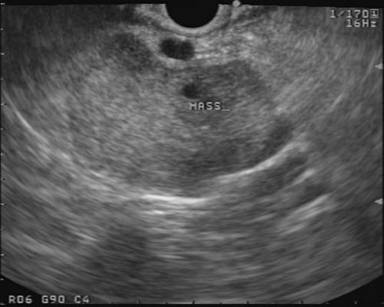

Main duct IPMN is typically easy to differentiate on EUS and ERCP due the diffuse dilation of the pancreatic duct, mural tumor growth and occasionally intraductal filling defects due to mucin production (Figure 4). EUS imaging of branched duct IPMN usually demonstrates visible communication of the cyst with the main pancreatic duct. However, in the absence of duct communication, branched duct IPMNs may be morphologically indistinguishable from mucinous cystic neoplasms. Endoscopic visualization of mucin extruding from a patulous papilla (referred to as "fish mouth deformity") supports the diagnosis. On EUS, any intraductal mass, mural nodule (Figure 5) or projections noted within the main duct or off a cyst wall should be sampled by FNA. If no visible lesions are noted, the main duct or branch can be punctured for cytology and tumor markers. Cytology usually reveals thick mucin but may be thin and completely acellular [54]. Occasionally, fragments of papillary mucinous epithelium can be seen on FNA or cytobrushings. Cyst fluid resembles that obtained from mucinous cystic neoplasm with a relatively elevated CEA; however, amylase tends to be higher due to the ductal communication.

Figure 5. EUS appearance of a cystic lesion in the body of the pancreas communicating with the main duct via a small side branch. The lesion has papillary projections and a solid mural nodule. |